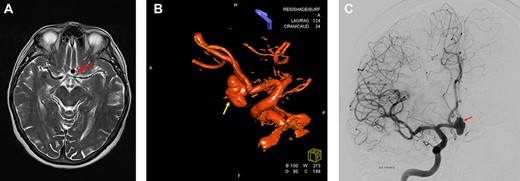

After pterional craniotomy on the right side, the anterior vasculature, optic nerves and chiasm were dissected, and all perforating vessels were preserved. The anteriorly directed part of the aneurysm was massively calcified, even ossified and adhered to the skull base at the level of the tuberculum sellae (see Fig. 2A and B). Thus, separating the aneurysm from the anterior skull base was not possible. The right A1 segment was temporarily clipped. The flow inside the aneurysm was assessed by means of micro-Doppler examination that showed a preserved intensive perfusion signal from the left side (Fig. 2B). The aneurysm was further dissected, but the right A2 segment could not be separated from the bulky, rigid aneurysm sack. Compression of the aneurysm was also not possible, and no clip could be positioned because of massive calcification of the aneurysm wall (Fig. 2A). After circumferential dissection and consecutive identification of all vessels as well as repeated attempts to compress the aneurysm and to restrain the flow, surgery was finally discontinued because of the increasing risk of aneurysm rupture in the case of further manipulation.

Intraoperative microscopic transsylvian view of the aneurysm. (A) Intraoperative microscopic transsylvian view of the aneurysm after the failed attempt to compress the calcified aneurysm with two suction devices (AN = aneurysm, R-ON = right optic nerve, SUC = suction, and R-A1 = right anterior cerebral artery). (B) Intraoperative microscopic transsylvian view of the aneurysm showing the assessment of the flow inside the aneurysm by means of micro-Doppler examination after temporary clipping of the right A1 segment. (AN = aneurysm, R-ON = right optic nerve, SUC = suction, DOPPLER = micro-Doppler, R-A1 and R-A2 = right anterior cerebral arteries).